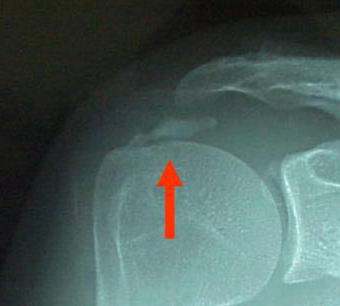

急に肩が痛くなって動かせない! 石灰沈着性腱炎- 古東整形外科・リウマチ科。

石灰沈着性腱板炎 石灰性腱炎の画像診断のポイント。